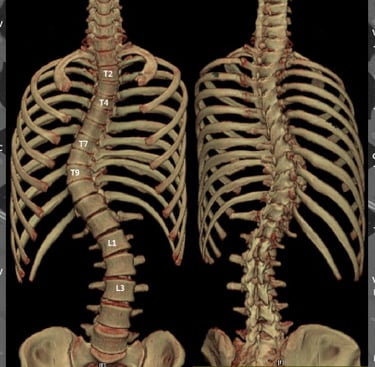

غالبًا ما يتطوّر الجنف بشكل تدريجي وقد لا يسبب ألمًا واضحًا في مراحله المبكرة. كثير من الأفراد — سواء الأطفال أو البالغين — قد لا يدركون إصابتهم بالجنف إلا بعد ملاحظة تغيّرات في وضعية الجسم أو وجود عدم تماثل واضح. ويساعد فهم العلامات الشائعة للجنف في تحديد ما إذا كان من المناسب إجراء تقييم مهني.

عند الانحناء إلى الأمام (مثل ربط الحذاء)، قد يبدو أحد جانبي القفص الصدري أو أسفل الظهر أعلى أو أكثر بروزًا من الآخر — وهي علامة شائعة على دوران العمود الفقري المرتبط بالجنف.

تساعد هذه النتائج الموضوعية على تحديد ما إذا كان الجنف موجودًا، وطبيعة انحناء العمود الفقري، وما إذا كانت هناك حاجة إلى رعاية إضافية — مثل المتابعة الدورية، أو إعادة التأهيل، أو استخدام الدعّامات — وفقًا للحالة.